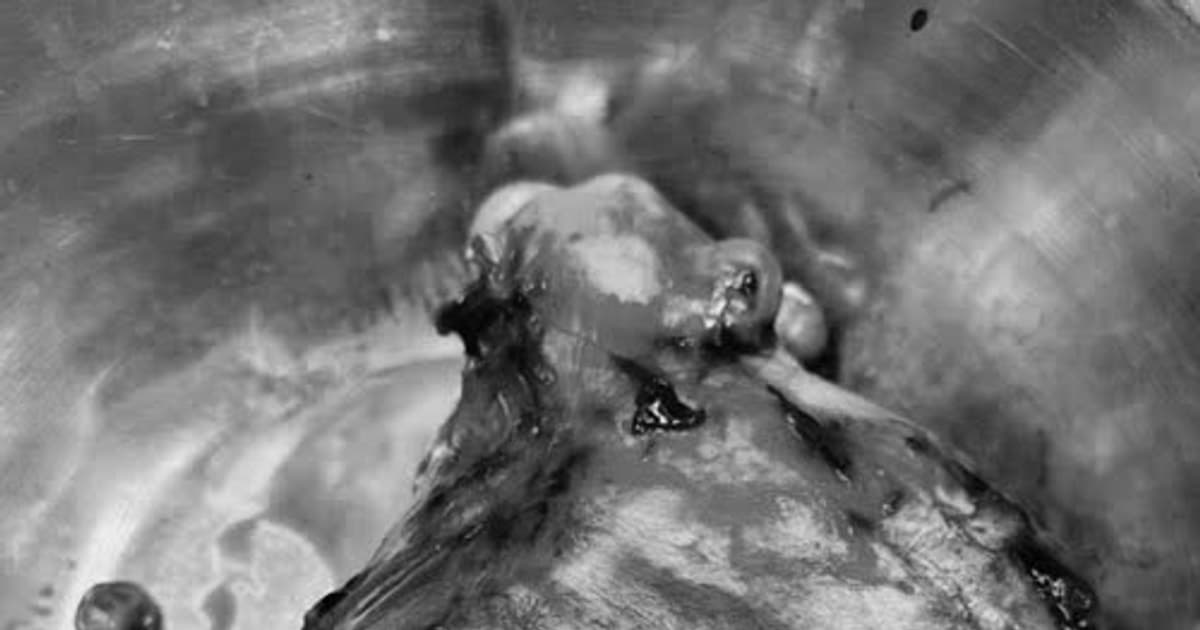

Cắt bỏ khối u xơ tử cung gần 3kg ở nữ bệnh nhân 47 tuổi

(CLO) Các bác sĩ Bệnh viện Việt Nam – Thụy Điển Uông Bí vừa phẫu thuật thành công loại bỏ khối u xơ tử cung nặng gần 3kg cho một nữ bệnh nhân 47 tuổi.